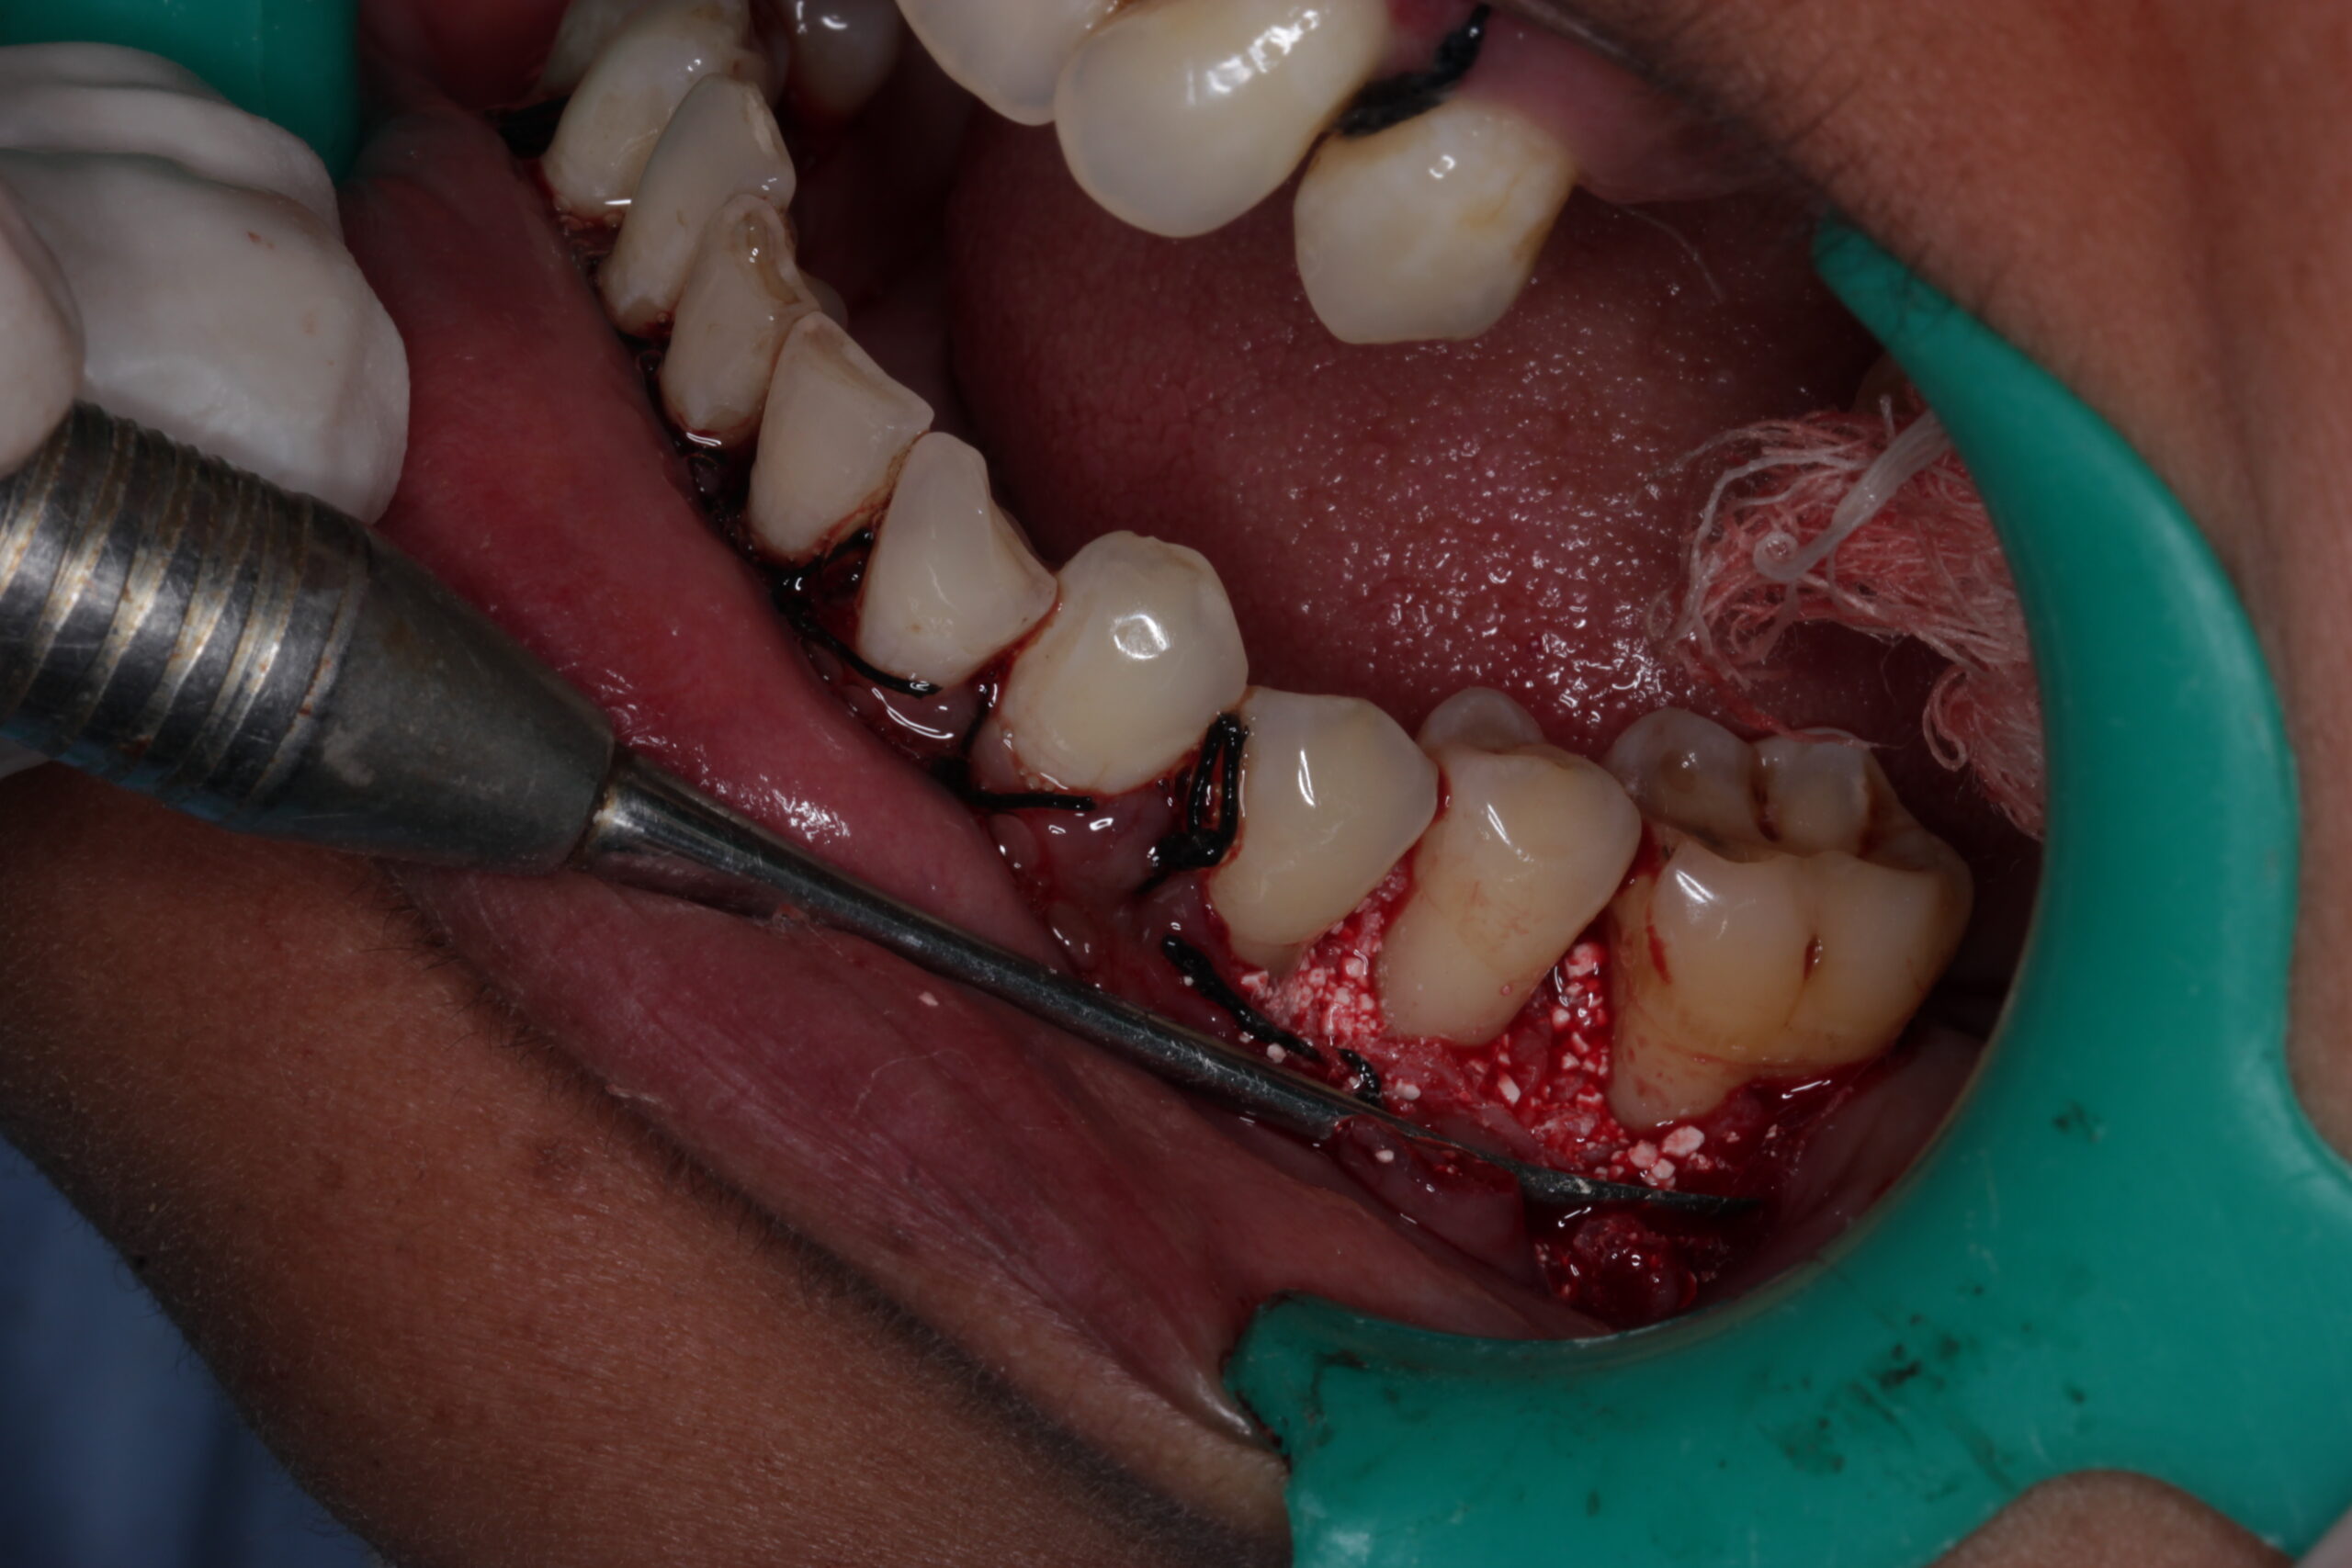

Flap Surgery

Flap surgery is a more advanced treatment used for severe gum disease. During this procedure, the gums are carefully lifted (or “flapped”) to access the underlying bone and tooth roots. The dentist will clean the area thoroughly, removing any plaque or tartar buildup, before reattaching the gums. This technique helps to reduce deep pockets around teeth, which are prone to infection.

• Gum Tissue Flap: The dentist makes an incision in the gum tissue to lift it, exposing the roots and the infected area underneath.

• Deep Cleaning: The exposed areas are cleaned meticulously to remove plaque, tartar, and bacteria from the tooth roots.

• Repositioning the Gums: After cleaning, the gums are placed back in position and sutured to fit snugly around the teeth.

• Post-Surgery Recovery: Post-operative care instructions are given to prevent infection and ensure proper healing.